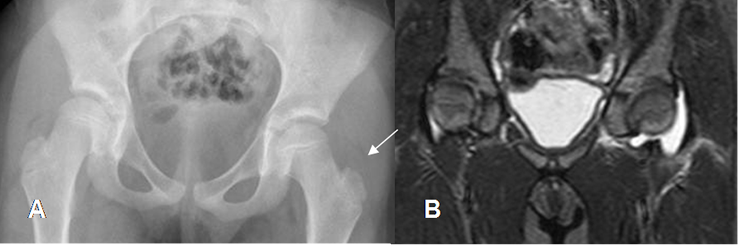

En la fase final hay destrucción articular, con anquilosis y edema de tejidos blandos. (16). (Fig 65 A y B).

Fig 63 C. Artritis séptica.

A: Rx pelvis AP. Desplazamiento del cojinete graso de la cadera, como signo de derrame articular. (Comparar con el contralateral).

B: RM coronal en STIR. Derrame articular, de donde se cultivó estafilococo aureus.